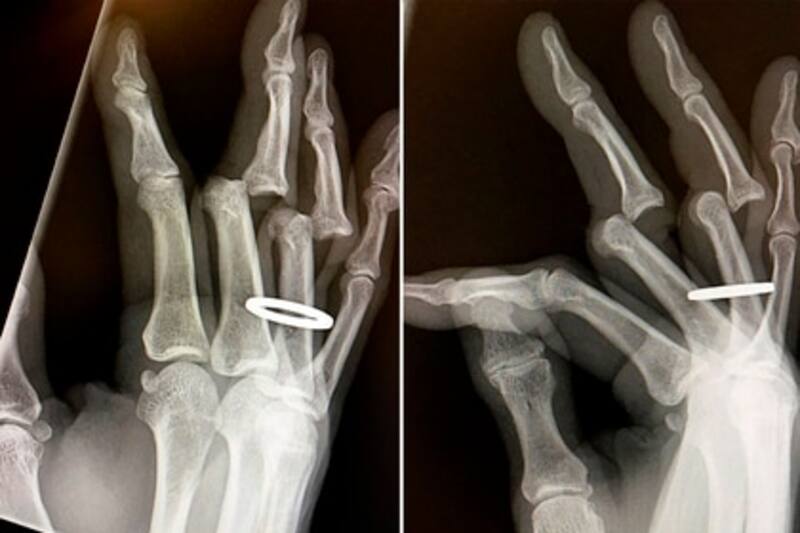

"Me asiganron de inmediato a una habitación cuando llegó una máquina de rayos X. Aparentemente, 'oscuro' es el color de la pérdida de circulación extrema. En 30 minutos mis dedos estaban de nuevo en su lugar y ya no estaban oscuros". señaló el skater.

Incluso, al momento de la lesión portaba su anillo, el cual debió ser cortado antes de volver a posicionar sus dedos.